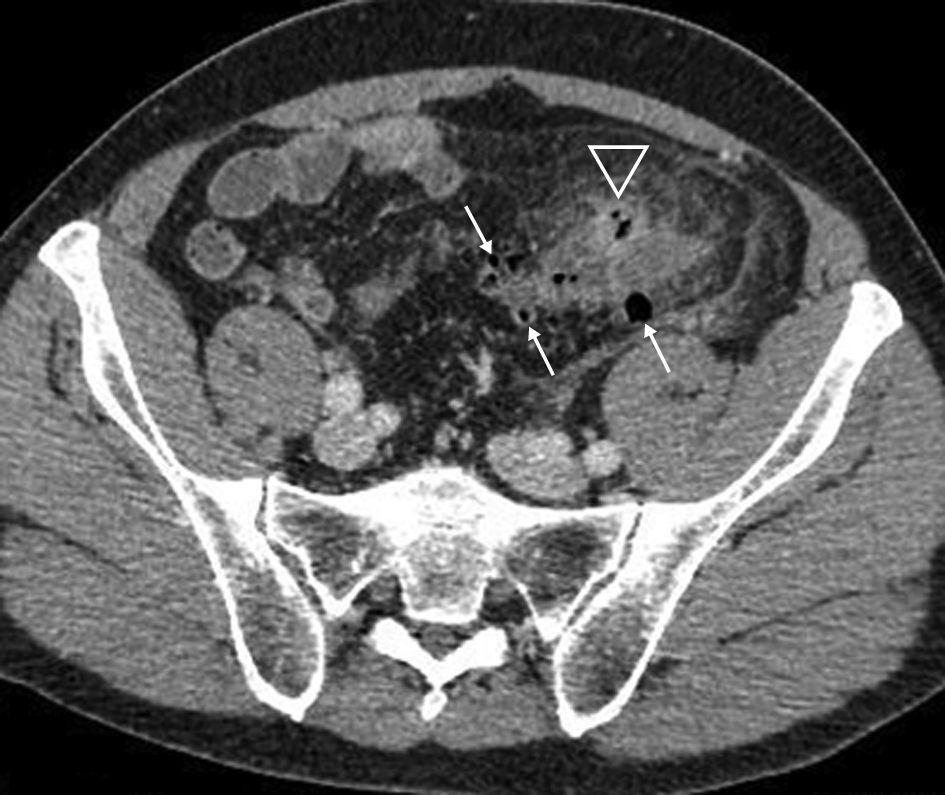

- La perforation du diverticule se manifeste par la présence d’air en dehors du tube digestif (pneumopéritoine) à proximité (figure 6.2) ou à distance du diverticule.

Fig. 6.2 Diverticulite compliquée d’une perforation (Hinchey 1).

Scanner au temps portal après injection de produit de contraste iodé. La paroi du côlon sigmoïde est très épaissie (∗). Il existe une infiltration de la graisse périsigmoïdienne en avant de celui-ci (flèches fines). La présence d’air en dehors du tube digestif (flèche épaisse) traduit la perforation de ce dernier, restant, dans ce cas, à proximité du diverticule.

Source : CERF, CNEBMN, 2022.